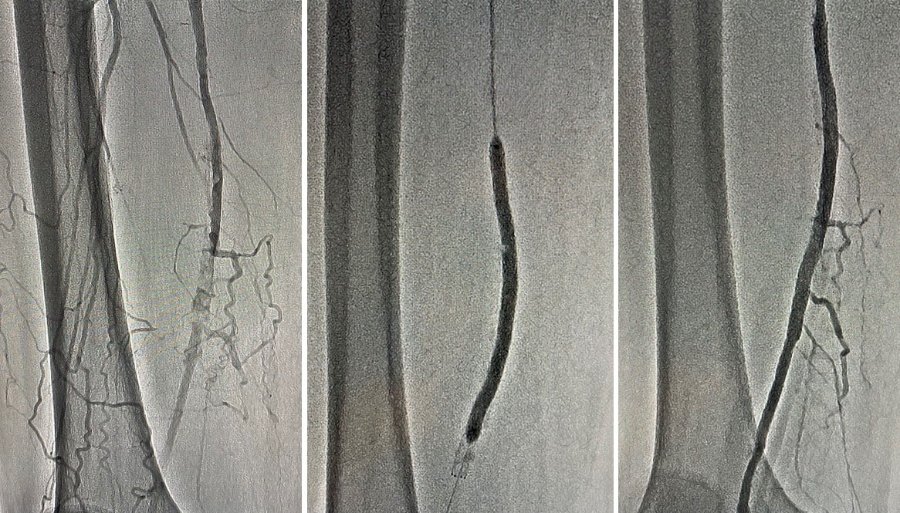

Після проведення ангіографії нижніх кінцівок діагностовано субоклюзію та оклюзію дистальних відділів поверхневих стегнових артерій - 100% і 98%. Команда ендоваскулярних хірургів провела стентування обох артерій через проколи в паху.

Операція пройшла успішно. Лікарям вдалося повністю відновити кровотік в судинах та запобігти втраті обох кінцівок. Нині біль в ногах пацієнта не турбує. На третій день після операції його виписали з лікарні.